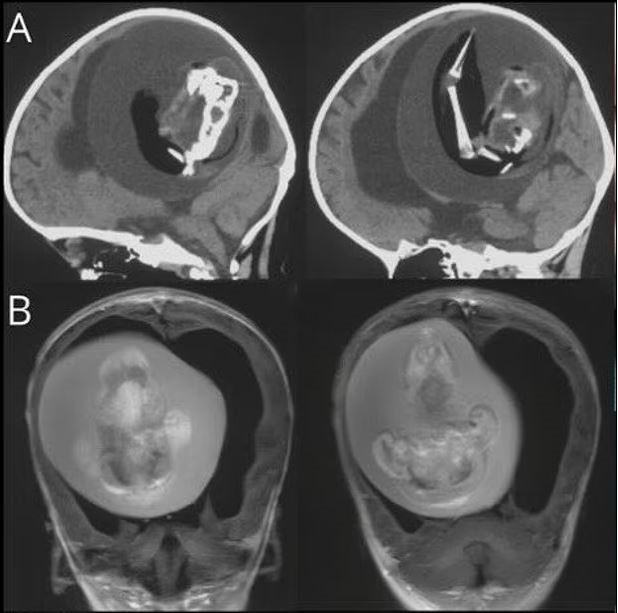

Çin'de bir yaşındaki bebeğin beyninden ikizinin fetüsü çıkarıldı. Bunun tarihte yalnızca birkaç kez yaşanan bir anomali olduğunu dile getiren uzmanlar, bebeğin kafatasının beklenenden daha geniş olması nedeniyle durumun fark edildiğini belirtti.

Tıp literatüründe yalnızca birkaç kez ortaya çıkan ilginç bir olay yaşandı. Çin'de bir yaşındaki bir bebeğin kafatasının beklenenden geniş olduğu ve motor becerilerinde sorunlar görüldüğü gerekçesi ile hastaneye kaldırılmıştı. Bebeği hastalığı şaşkına çevirdi.

Bebeğin beyninin sıkıştığı ve içinde sıvı birikimi olduğu tespit edilince ileri incelemeler yapıldı.

İncelemeler sonucunda bebeğin bir ikiz kardeşi olduğu ancak anne karnında gelişemediği için kardeşinin beyninde sıkıştığı ortaya çıktı.